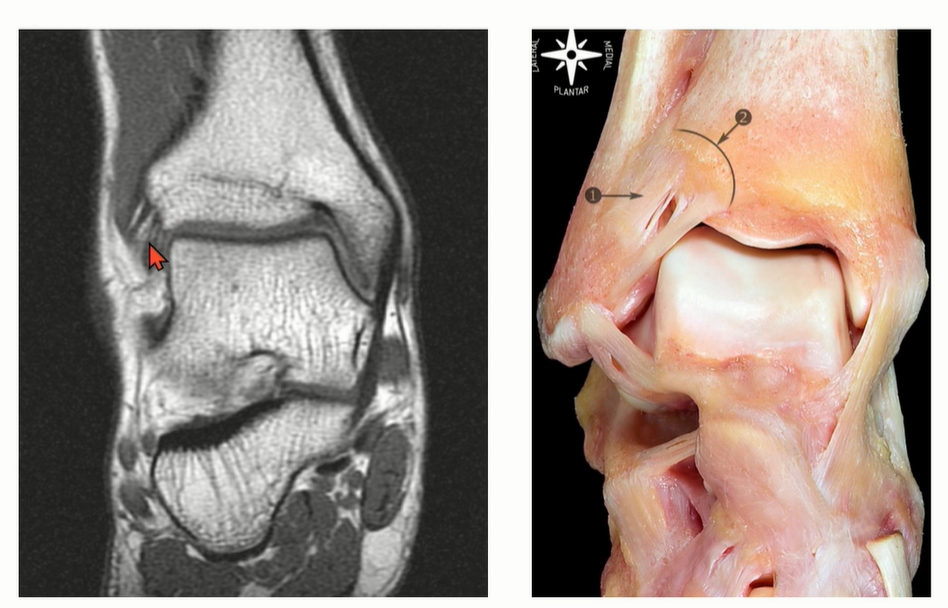

4-2. ATTFL

Tibia plafond의 anterolateral tubercle에서 시작해서 distal fibula에 붙고, 비스듬하게 여러 가닥으로 구성되어 있다.

AITFL의 가장 inferior bundle은 main bundle에서 떨어져 있는데, 이 fiber를 Bassett's ligament 라고 부른다. Talus와 impinge를 일으키기도 하는데, anterolateral ankle impingement를 뜻함.

MRI에서는 coronal cut에서 AITFL 를 관찰하기 용이하다. Multi-fascicular 구조이기 떄문에, Tear로 오인하면 안됨.

특히 Axial cut에서는 일부 cut에서 discontinuity 가 관찰될 수 있는데, oblique한 주행 방향으로 인한 정상 소견일 수 있다는 것을 염두해야 한다.